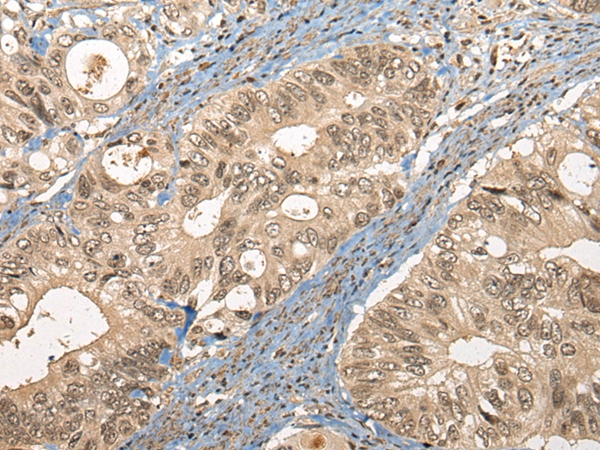

The image on the left is immunohistochemistry of paraffin-embedded Human liver cancer tissue using 46413(CC2D1A Antibody) at dilution 1/35, on the right is treated with synthetic peptide. (Original magnification: x200)

The image on the left is immunohistochemistry of paraffin-embedded Human colorectal cancer tissue using 46413(CC2D1A Antibody) at dilution 1/35, on the right is treated with synthetic peptide. (Original magnification: x200)